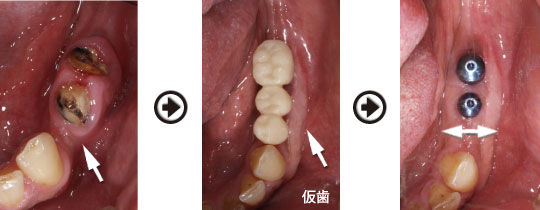

歯周病 抜歯 約半年後、インプラント埋入